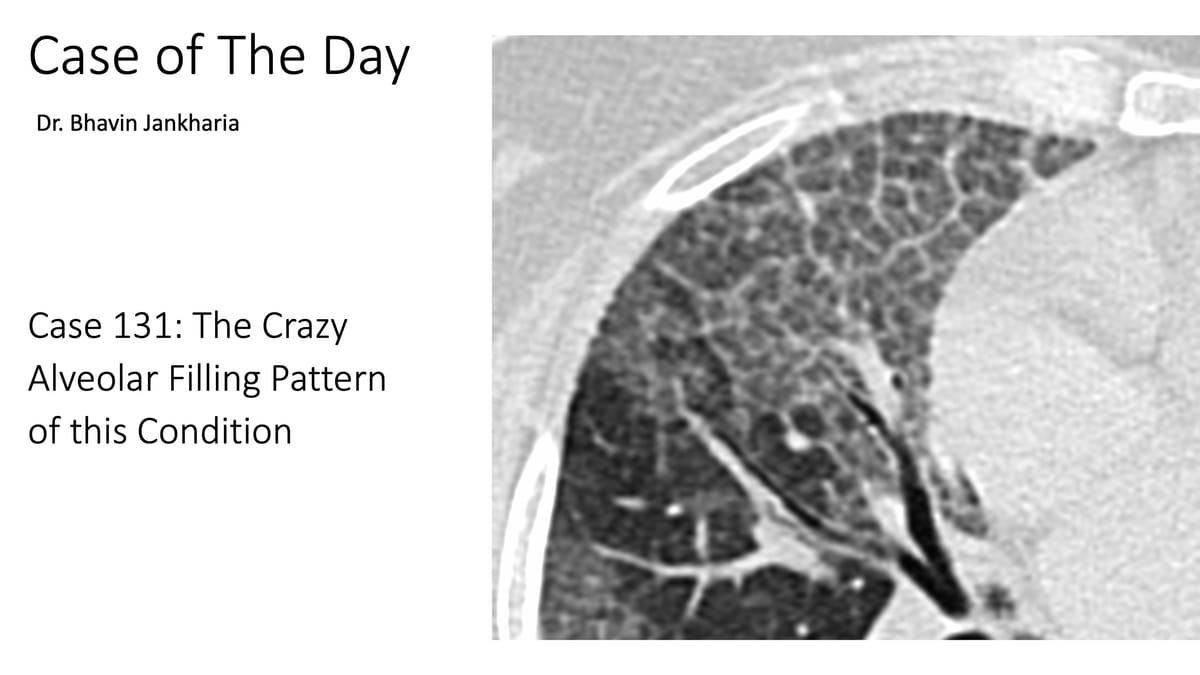

COD 131 - The Alveolar Filling Pattern

The diffuse crazy-paving pattern is quite distinctive in its classic, typical form.